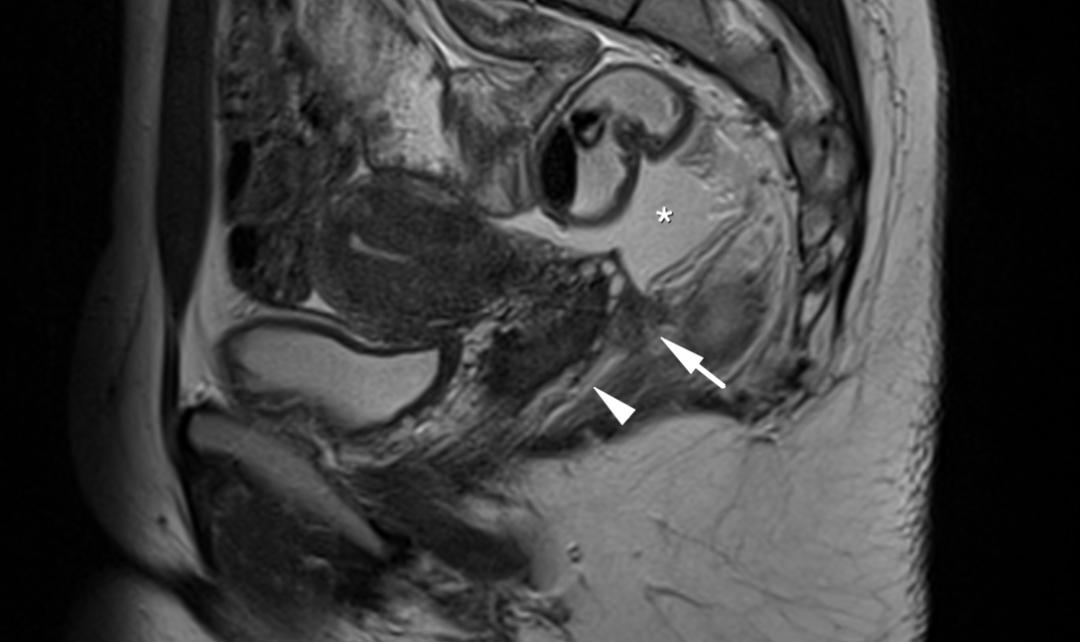

CASE 8

T2WI 矢状位显示子宫颈右后方结节样低信号,其内微小高信号结节,边缘毛糙,累及右侧子宫骶韧带、阴道后穹窿、直肠壁; T1WI 轴位可见小结节高信号,提示出血。